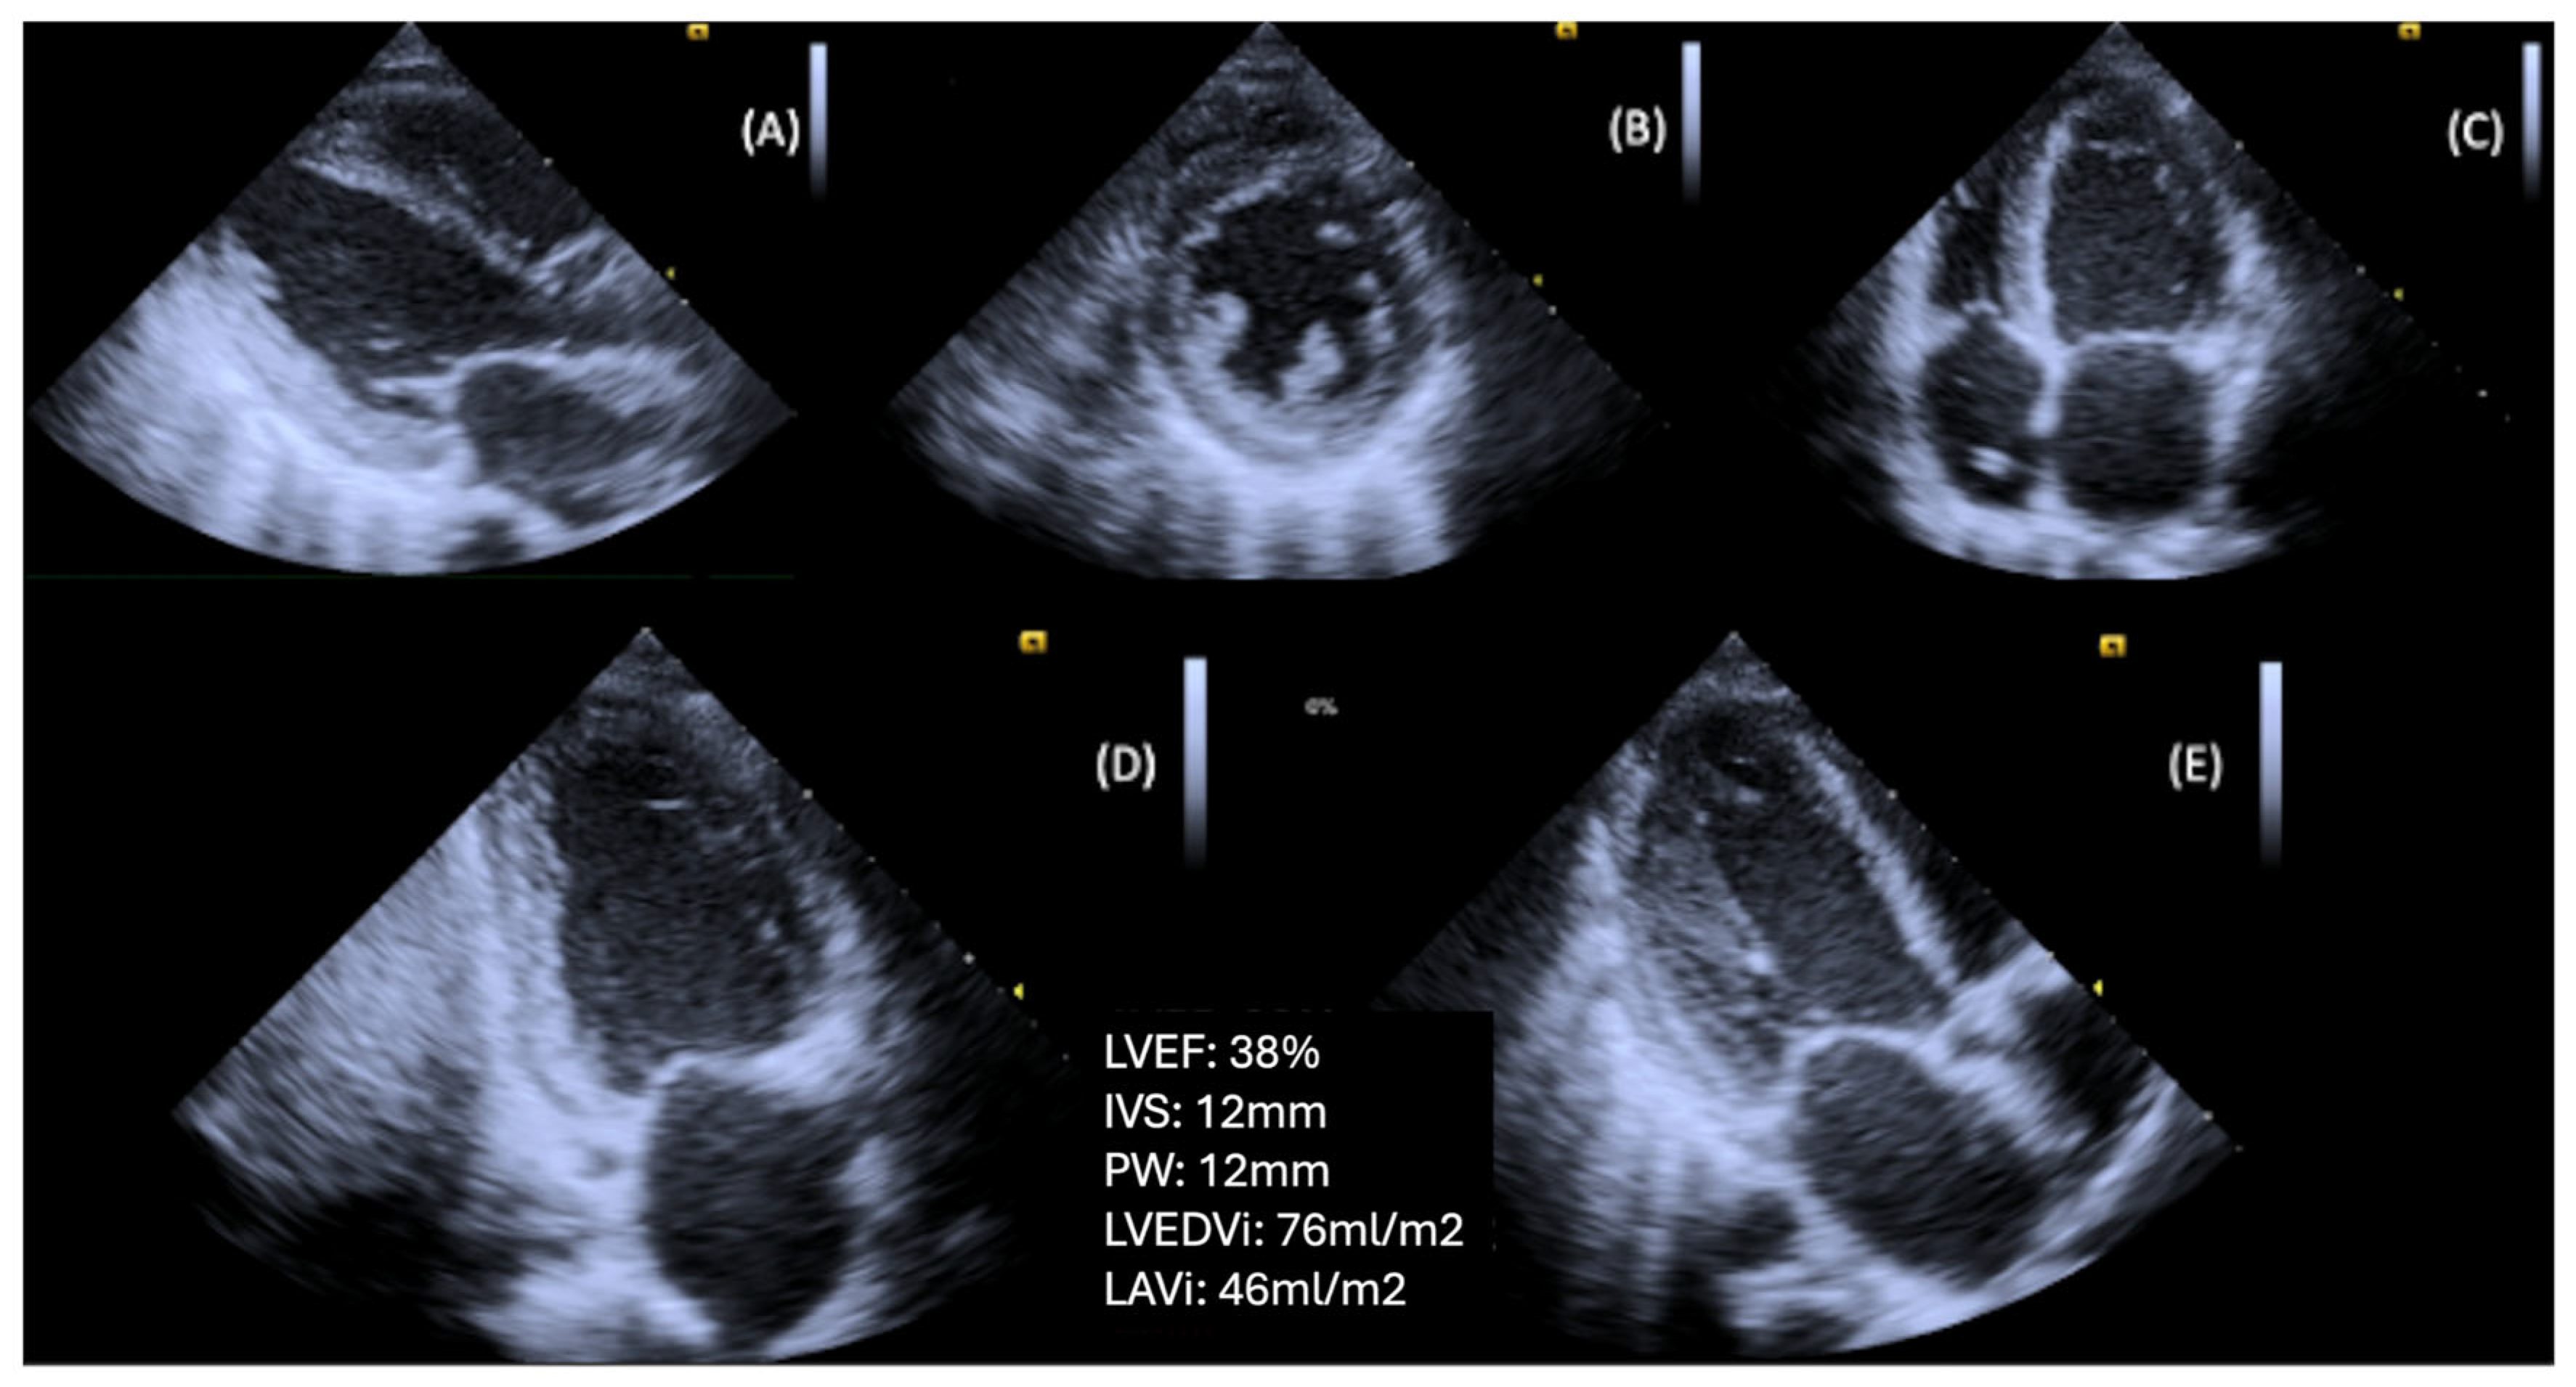

Diastolic dysfunction in individuals with DM is associated with a worse prognosis, as these patients face a higher risk of developing HF, compared to their counterparts without diastolic dysfunction [45]. Optimizing DM treatment and reducing HbA1c levels may lead to improvements in diastolic dysfunction, potentially delaying the progression to HF [56] (Figure 1).

3.3. LV Systolic Dysfunction

Systolic dysfunction is a later manifestation, usually occurring after diastolic dysfunction in diabetic patients. DBCM, in its early stages, includes a latent subclinical period characterized by structural and functional abnormalities, including LVH, fibrosis, stiffness, and cell-signaling disruptions. These pathophysiological changes often progress to systolic dysfunction and eventually lead to a clinical HF [3,57]. Subtle systolic dysfunction is often not detected using standard two-dimensional echocardiography techniques [58]. Advanced imaging modalities, such as TDI, speckle-tracking echocardiography (STE), and GLS assessment, are more sensitive and better suited for identifying early impairments in systolic function. In DM patients with normal conventional parameters [LVEF, fractional shortening (FS)], it appeared that they present a significant decrease in both longitudinal and radial systolic strain values by STE [59]. More recent studies showed that subclinical myocardial dysfunction with a progressive decline in GLS was observed during follow-up using 2D and 3D-STE, independent of other cardiovascular risk factors, while no significant changes were noted in global circumferential or radial strain [60]. Ceyhan et al. showed that there is systolic and diastolic LV dysfunction even in prediabetic patients, as in patients with diabetes, by using the longitudinal peak systolic strain and the peak systolic and diastolic strain rates [61]. Finally, Leung et al. reported possible improvement in GLS after optimization of treatment and reduction in HbA1c [56].

Prolonged cumulative exposure to uncontrolled DM from early adulthood to middle age is a risk factor for adverse LV remodeling and subclinical LV dysfunction, initially diastolic and eventually systolic. The duration of DM may predict clinical HF, including both preserved and reduced LVEF, later in life [36]. A 1% increase in HbA1c is associated with an 8% higher risk of HF [62]. Presumably, the early commitment to intensive glucose lowering can slow the progression of DBCM and reduce the risk of developing clinical HF (Figure 2).